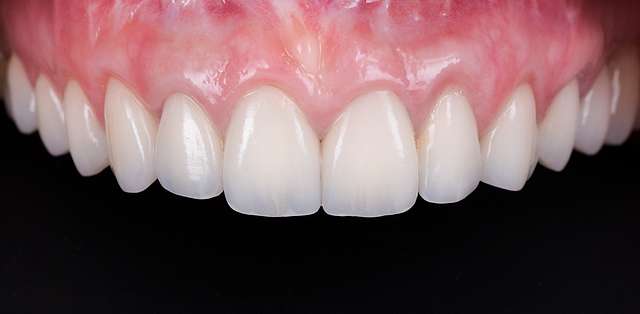

Using tissue grafts to correct tissue defects

Using tissue grafts to correct gingival levels or cover recessions